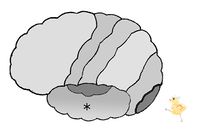

図は、左の大脳皮質を左から見た図です。

大脳皮質の図において、*印は 前頭葉 頭頂葉 後頭葉 側頭葉 である。

大脳皮質の図において、*印は 前頭葉 頭頂葉 後頭葉 側頭葉 である。

大脳皮質の図において、*印は 前頭葉 頭頂葉 後頭葉 側頭葉 である。

大脳皮質の図において、*印は 前頭葉 頭頂葉 後頭葉 側頭葉 である。

大脳皮質の図において、*印は 中心前回 中心後回 である。

大脳皮質の図において、*印は 中心前回 中心後回 である。